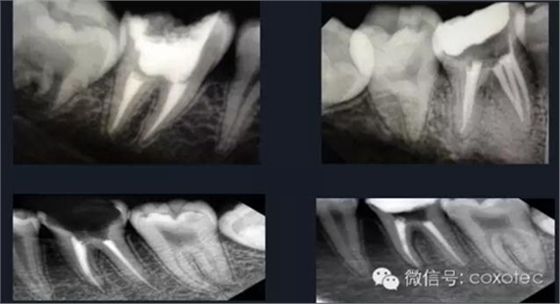

熱牙膠根管充填技術(shù)是利用牙膠加熱軟化后具有流動(dòng)性的特點(diǎn),使根管充填的效果更理想。

熱牙膠加壓充填技術(shù)是在加熱軟化牙膠尖的同時(shí),通過(guò)側(cè)向或(和)垂直向的壓力,將牙膠壓緊以嚴(yán)密封閉根管系統(tǒng)。以替代傳統(tǒng)冷的側(cè)方加壓充填的一種儀器。

由于它可以快速精確,密實(shí)的三維根管充填而受到醫(yī)生廣泛推崇,必將為根管充填帶來(lái)革命性的影響。

熱牙膠充填要點(diǎn)

①選擇符合根管錐度的主牙膠尖,標(biāo)記工作長(zhǎng)度后切斷牙膠尖端

0.5~1mm,并有確實(shí)的回拉感。

②去除距離根尖孔3~5MM以上牙膠。

③選擇合適的攜熱器,確定攜熱器工作長(zhǎng)度為根管工作長(zhǎng)度減去3-5毫米。

④選擇合適的垂直加壓器,并確定加壓器工作長(zhǎng)度,多把加壓器長(zhǎng)度遞減配合使用。

⑤選擇合適的熱牙膠充填器頭,標(biāo)記好需要充填的長(zhǎng)度。

⑥將根管內(nèi)注入樹(shù)脂類根管封閉劑后,再將牙膠尖放入根內(nèi)。

⑦使用手用加壓器垂直擠壓致密,垂直加壓器應(yīng)該從大號(hào)至小號(hào)。

⑧注射手法:輕,穩(wěn),慢